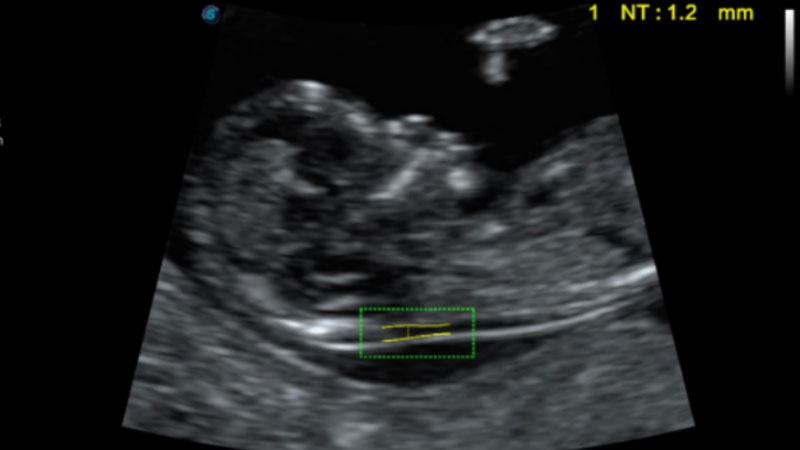

自动识别颈项透明层并获得NT值,为早孕胎儿畸形筛查提供有效测量工具,提高诊断效率和诊断信心。